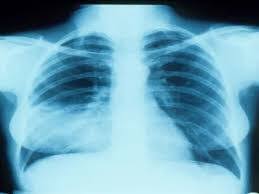

لتشخيص الإصابة بانخماص الرئة، قد يكون كل ما يلزم من فحص الطبيب والأشعة السينية الواضحة على الصدر. ورغم ذلك، يمكن إجراء اختبارات أخرى لتأكيد التشخيص أو تحديد نوع أو شدة انخماص الرئة، وتتضمن: